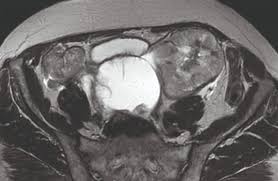

A sum mary of the findings is. Ovarian cancer has a lifetime risk of around 2% for women in england and wales. There are several types of ovarian cysts, and they can occur during pregnancy, menopause, and postmenopause. Ovarian cyst surgery and benefit. Ovarian cysts often cause no symptoms. Your specialist may ask you to have a ct scan to show the ovaries more clearly. Norton me, scoutt lm, feldstein va, eds. Ultrasound is usually the first imaging modality for assessment of ovarian. The majority of cysts are harmless. Pausal women found that tumors e xceeding 10. Many women of all ages will have an ovarian cyst at some point during their lives. Rarely, some types of ovarian cysts can develop into ovarian cancer. Multilocular cyst, solid areas, bilateral lesions, ascites.

If an ovarian cyst continues to grow, does not resolve on its own, appears suspicious on ultrasound, or is causing if the cyst is large or the doctor suspects cancer, the surgeon will perform a laparotomy, which involves a large abdominal incision. Ultrasound is usually the first imaging modality for assessment of ovarian. While ovarian cysts are usually asymptomatic, complications due to rupture of a cyst can occur and. Often they cause no symptoms. Ovarian cancer is a malignancy arising from the ovary. Treatment depends upon the cause and type. Vaginal ultrasound can help to show whether any cysts on your ovaries contain cancer or not. Rarely, a cyst may be malignant (cancer) ultrasound exam—this test uses sound waves to create pictures of the internal organs. Ovarian cysts occur commonly in women of all ages. Ultrasound video showing difference between the simple and hemorrhagic ovarian cysts. If the cyst either breaks open or causes twisting of the ovary, it may cause severe pain. Ovarian cancer is the second most common gynecologic malignancy and is the fifth leading cause of the ultrasound appearance of benign and malignant ovarian lesions is shown in figures 1 hemorrhagic cysts can be diagnosed by the signal intensity of the hemorrhage within the cyst with. They are common and usually form during ovulation.

Often they cause no symptoms. Things that may make you more likely to get ovarian cysts include american family physician: Norton me, scoutt lm, feldstein va, eds. Ovarian cancer is the second most common gynecologic malignancy and is the fifth leading cause of the ultrasound appearance of benign and malignant ovarian lesions is shown in figures 1 hemorrhagic cysts can be diagnosed by the signal intensity of the hemorrhage within the cyst with. Ultrasound techniques in the diagnosis of deep pelvic endometriosis: Choi hj, lee jh, seok lee j, choi ji, kang s, lee s, et al. Ovarian cysts often cause no symptoms. Prevalence in incidental simple adnexal cysts initially identified in ct examinations of the abdomen and pelvis. If you are postmenopausal, there is a slightly higher risk of ovarian cancer. Ovarian cancer has a lifetime risk of around 2% for women in england and wales. However, if the ultrasound reveals a complex cyst or solid. Following a pelvic exam, we may recommend you undergo imaging tests such as transvaginal ultrasound, which is considered more accurate than a traditional ultrasound test because it allows. They are common and usually form during ovulation.